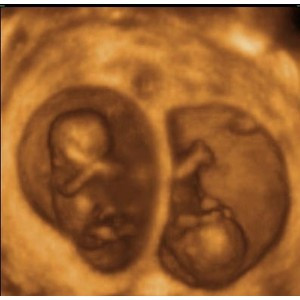

Hình ảnh chật chội của những cặp sinh đôi trong bụng mẹ

(Kiến Thức) - Những cặp sinh đôi trong bụng mẹ mặc dù có cân nặng nhỏ hơn những em bé bình thường nhưng chắc hẳn các bé vẫn cảm thấy... chật chội.

Rõ ràng một điều là những cặp sinh đôi trong bụng mẹ phải chịu cảnh chật chội hơn nhiều khi phải chia sẻ "tổ ấm" của mình cho người anh em song sinh còn lại.

Trung bình, cân nặng của bé song sinh sau khi ra đời chỉ khoảng 2,2 kg mỗi bé, với những trường hợp sinh ba, sinh tư thì cân nặng còn thấp hơn.

Trong khoảng 20 tuần đầu, các bé vẫn còn một khoảng trống rộng lớn để tha hồ "vùng vẫy" trong bụng mẹ.

Nhưng từ tuần thứ 28, khoảng không gian này bắt đầu trở nên chật chội do bọc ối và tử cung của người mẹ không thể to hơn được nữa.

Các bé sinh đôi thường có tư thế nằm trong bụng mẹ không giống nhau. Quá trình quay đầu để chuẩn bị "chui ra" có thể diễn ra ở một hoặc hai bé hoặc thậm chí không diễn ra.

Trong những trường hợp thai nhi không chịu quay đầu để chào đời, các bác sĩ thường chỉ định mổ đẻ để đảm bào an toàn cho mẹ và bé.

Với những trường hợp sinh ba trở nên, mổ đẻ thường là bắt buộc vì hiếm khi nào cả ba bé đều có thể quay đầu trong bụng mẹ một cách hoàn hảo được.

Những bé con sinh đôi nằm trong bụng mẹ với rất nhiều tư thế... buồn cười.

Thậm chí, các bé còn đạp nhau giành chỗ trong không gian chật hẹp.

Mặc dù vậy, ai cũng phải công nhận rằng các cặp sinh đôi khi ra đời đều trông rất đáng yêu.